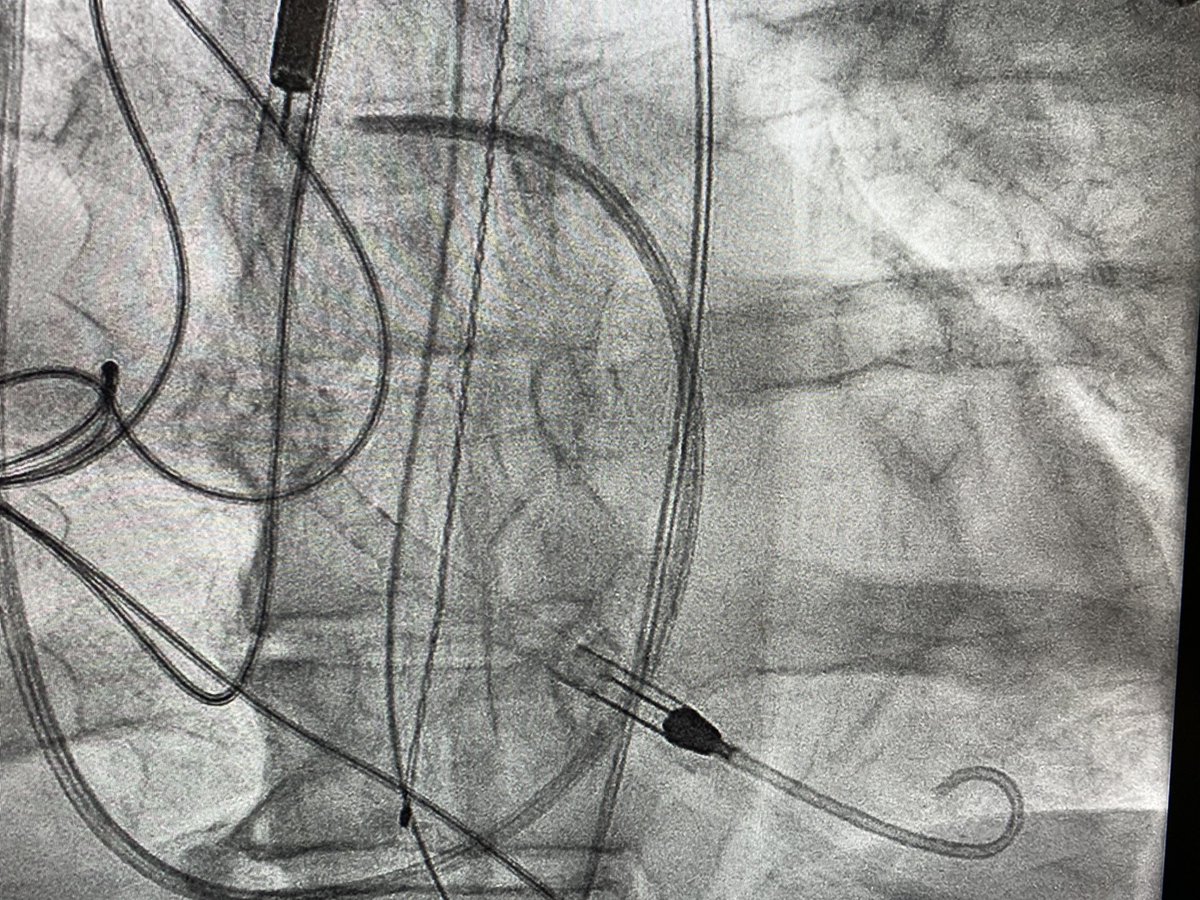

3/7 Impella observed going in. Take a moment to remove slack, achieve stable device position. Always place Swan with Impella in Shock...

4/7 Quick single-access (a la @jason_wollmuth et al) run-off angiogram at the very end confirming distal flow before removing peel-away sheath (or can perform via Radial access) to assess need for antegrade perfusion catheter...

5/7 Remove peel-away sheath. Cinch Perclose around leave-in sheath. Suture sheath in at appropriate angle (after shallow initial access [cantalever principle a la @J_M_McCabe]) and with sutures placed cranially to preserve forward sheath momentum...